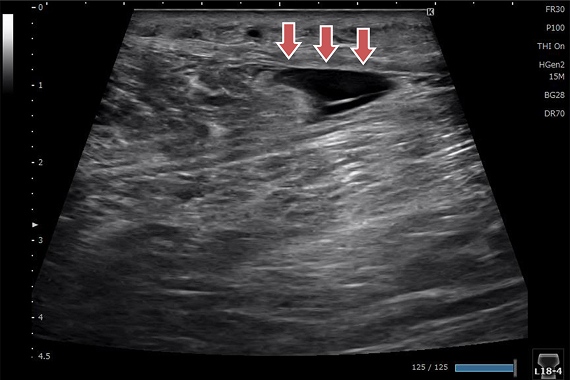

肋骨骨折

レントゲンでは肋骨骨折の評価は難しいですが、エコーでははっきりわかります。